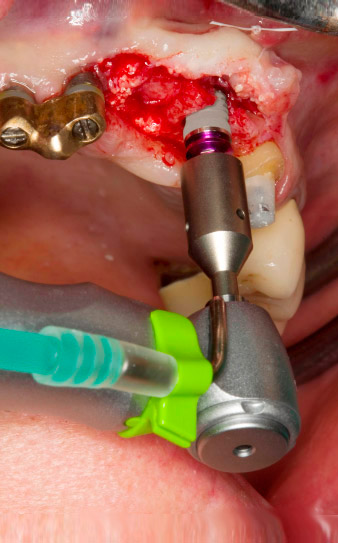

pilot drilling is performed with the new Implantmed and the WS-56 L contra-angle handpiece

Fig. 2: Two months later the pilot drilling is performed with the new Implantmed and the WS-56 L contra-angle handpiece (programme P1, ratio 1:1). The cooling is performed via the spray tube positioned on the left (for right-handed users).

Following primary healing, the soft tissues were shaped using the basally lined bridge. Two months later the site was exposed by a slightly palatal alveolar ridge incision (Fig 2). The dimensions of the alveolar bone proved to be sufficient at position 22. Figures 2 and 4 show the preparation of the implant bed, the tapping and the implantation using Implantmed.